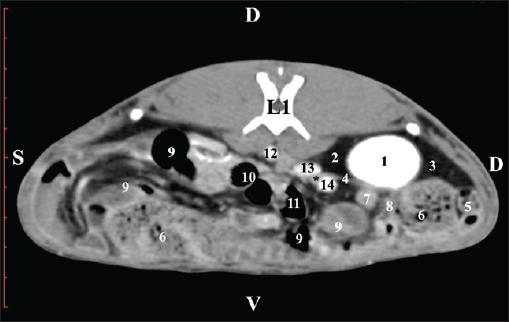

Post-contrast CT examination at the L1 level did not clearly distinguish the cortex from the medulla of the examined organ. The kidney appeared as a uniform oval hyperattenuated soft tissue, adjacent to the hypoattenuated lobus hepatis dexter and lobus caudatus. The renal capsules—capsula fibrosa and adiposa—were not differentiated. The large blood vessels, the beginning of the ureter, and the right adrenal gland were seen medial to the renal kidney (Fig. 15).

Fig. 15. Post-contrast computed tomography (CT) anatomical scan of the regio abdominis cranialis at the L1 level. (1) Ren dexter; (2) lobus hepatis dexter; (3) lobus caudatus (proc. caudatus); (4) ureter; (5) jejunum; (6) cecum; (7) pars descendens of the duodenum; (8) ileum; (9) colon ascendens; (10) colon transversum; (11) colon descendens; (12) aorta abdominalis; (13) v. cava caudalis; (14) a. renalis; (*) gl. adrenalis dextra.